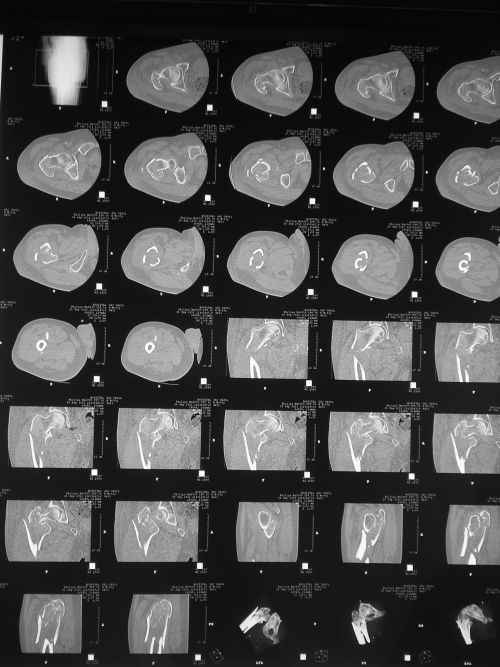

Чрезвертельный перелом правого бедра

Пациент 64 лет, поступил к нам 20.09.11. Сбит автомобилем. Сейчас на скелетном вытяжении. На КТ видно раздробленность черезвертельной зоны в саггитальной плоскости и вовлеченность шейки. Гамма? LCP?

В чем сомнения? Перелом распространяется на диафиз, так что оптимально - длинный проксимальный гвоздь, 3 разреза по 1,5-2 см, операция 20-30 мин. DHS или другие пластины менее предпочтительны. То, что область вертела имеет какие-то линии раскола, с гвоздем не имеет никакого значения. Нужно зафиксировать проксимальный фрагмент (головка-шейка) к диафизу в правильных взаимоотношениях, неважно, что там между ними.

Приветствую,коллеги.Учитывая подвертельную распространённость зоны перелома, имеются все показания для интрамедуллярной конструкции. DHS в данном случае работать не будет, как вариант возможно использовать DCS или клинковую пластину 95 градусов.